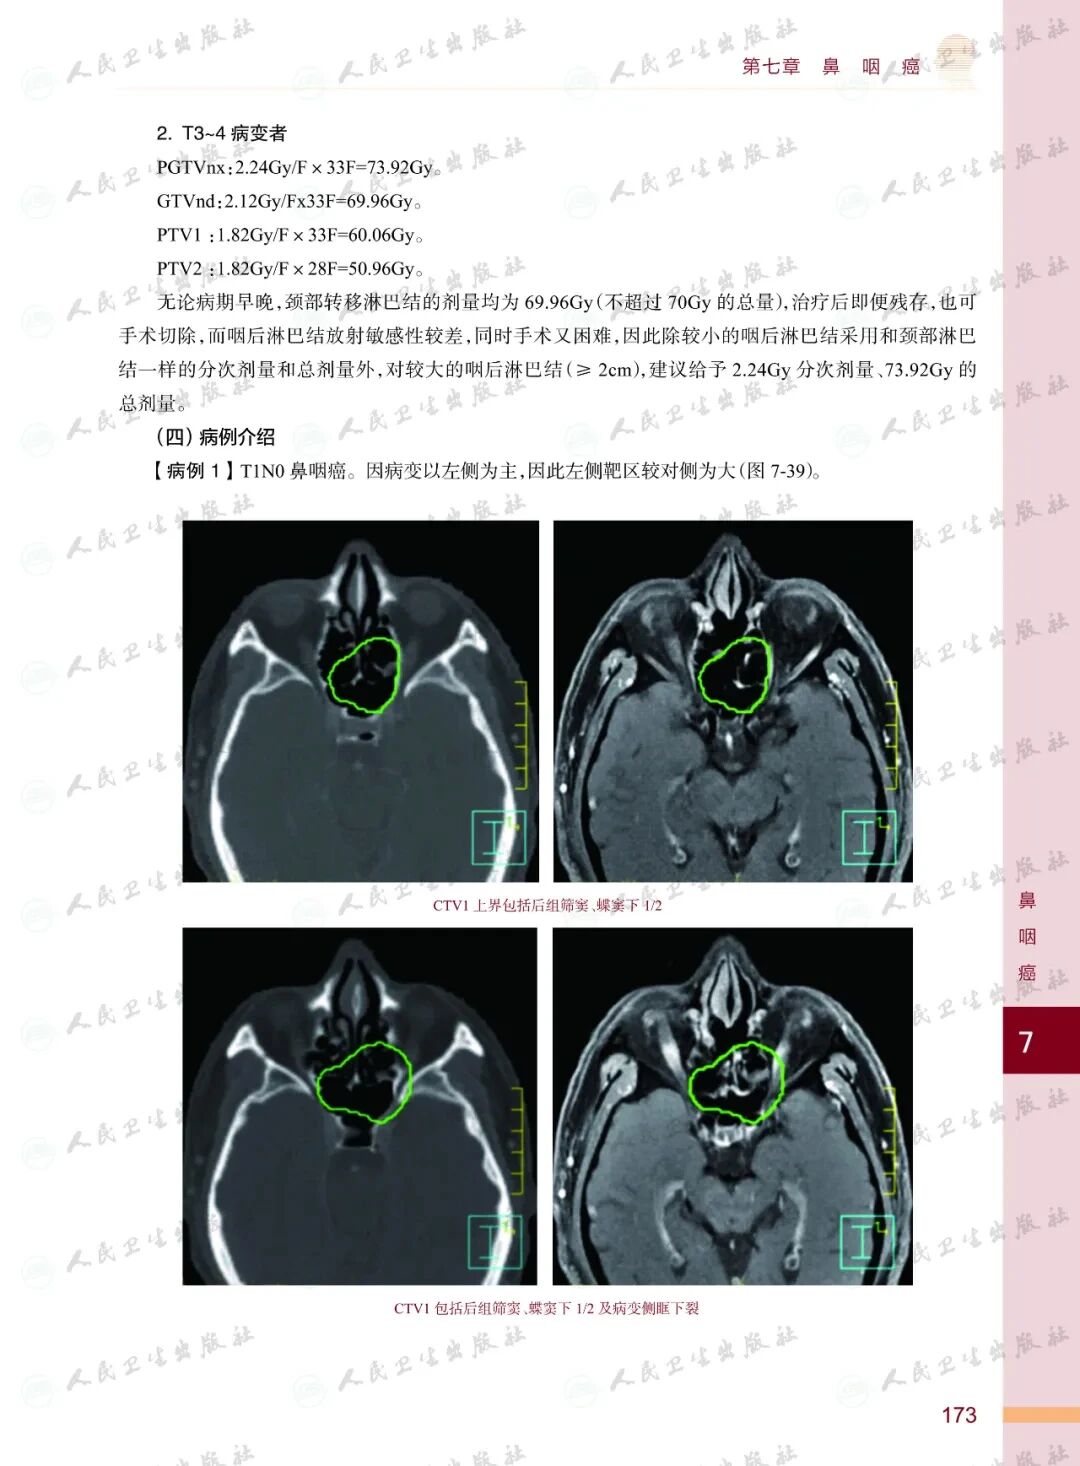

《头颈部肿瘤放射治疗图谱》

——不止是图谱,更是随唤随应的临床良师